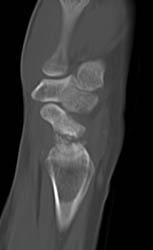

Scaphoid Fracture